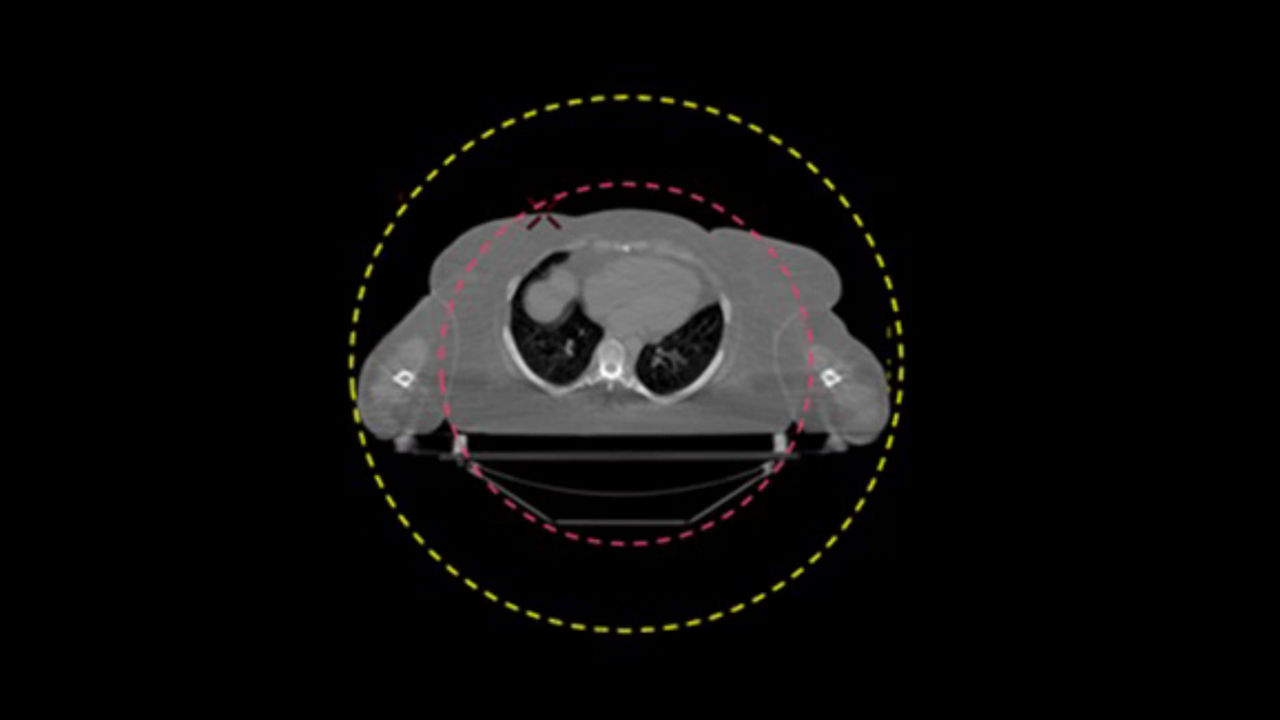

Streamline and automate your RT planning workflow.

<p>Auto Segmentation</p>

<p>Deviceless 4D</p>

<p>Advantage 4D</p>

<p>Prospective Gating</p>